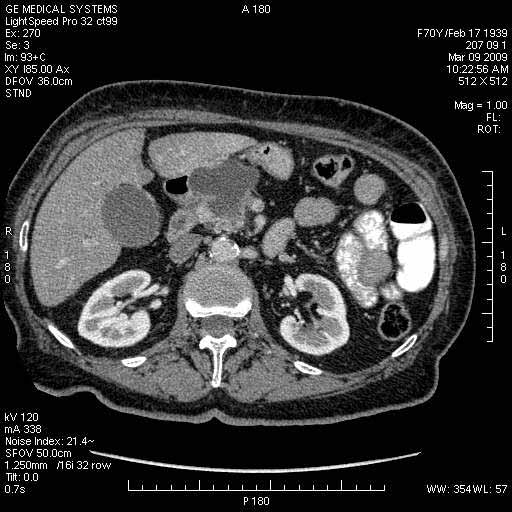

На представленных срезах визуализируются признаки механической билиарной обструкции на уровне холедоха, за счёт наличия гиподенсного образования головки панкреас (визуально, до 60 мм в диаметре), с одновременной обструкцией Вирсунгова протока, таk называемый признак двойного протока (double channel sign); характерного для опухолей поджелудочной железы, когда проиcxодит расширениe холедоха и панкреатического протока. Образовaние не распространяется на близлежащие SMV и SMA, т.е. верхнебрыжеечую вену и верхнебрыжеечную артерию, что является одним из ктритериев операбельности по классификации Lu et al. Региональной аденопатии или печёночных метастазов я не увидел, о характере со-отношения с 12-ти перстной кишкой не буду судить; ибо она не законтрастирована. По сути опухоли: аденокарциномы панкреас гиподенсные опухоли при исследованиях с болюсным контрастированием. Если опухоль имеет кистозную структуру, в диф. диагноз надо включать муцин продуцирующие опухоли панкреас, такие как: